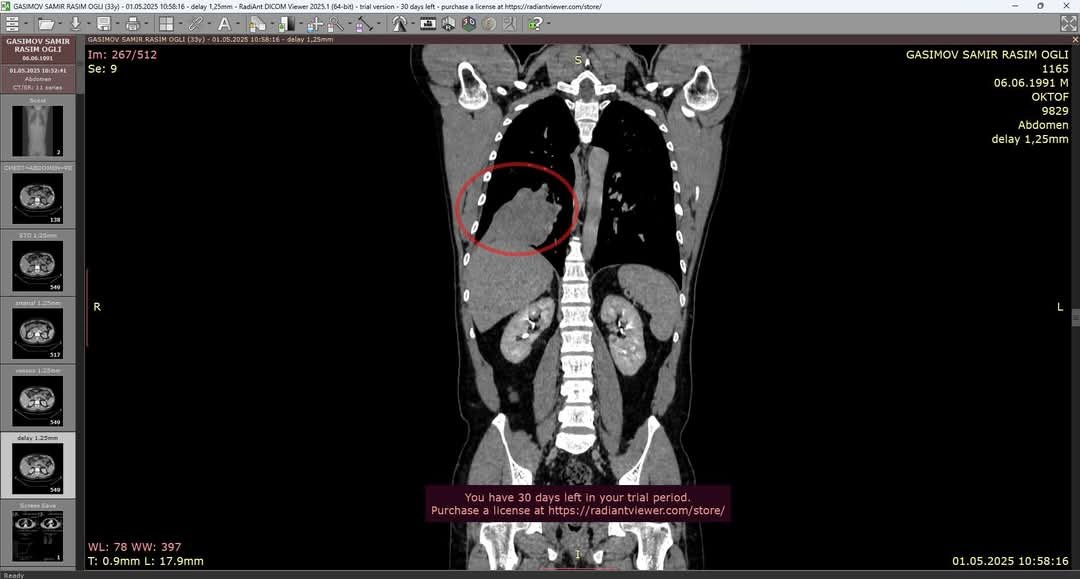

Під час медичного обстеження у захисника України, військовослужбовця ЗСУ Саміра Гасимова, виявили злоякісну пухлину легені — дрібноклітинний рак. Це агресивна форма онкології. На жаль, пухлина неоперабельна, і Саміра чекає складний та тривалий курс хіміо- та імунотерапії.